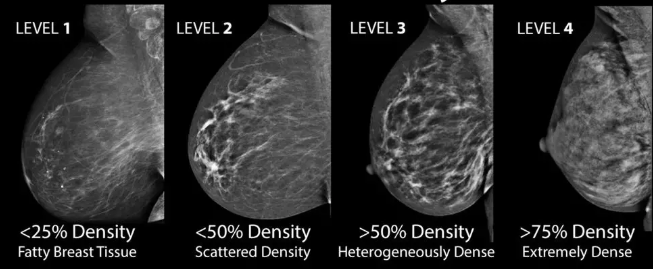

一项研究报告说,DBT筛查虽无乳腺癌筛查的主要指南的支持但应用率翻番。出国看病机构爱诺美康了解到,美国耶鲁医学院Richman等报告,尽管缺乏乳腺癌筛查的主要指南的支持,但在过去几年中,数字乳房X线照相术(DBT)或3D乳房X线照相术的使用增加了两倍多。

结果显示,DBT筛查率从2015年的12.9%增加到2017年的43.2%。在同样的3年研究中,DBT作为乳腺癌的主要筛查模型的医院数量(该方法的筛选应用率)超过50%)增加九倍,从4.6%增加到41.8%,其使用率是家庭收入中位数越高,受教育程度越高,白人居民的比例越高。

出国看病机构爱诺美康介绍,加利福尼亚大学戴维斯分校的Melnikow教授指出,在目前的临床实践指南中,包括美国预防服务工作组和美国癌症协会的筛查指南,DBT不是常规推荐,因为其大部分数据都来自于观察性研究。 然而,美国乳房外科医生协会和美国放射学院的指南支持使用DBT。